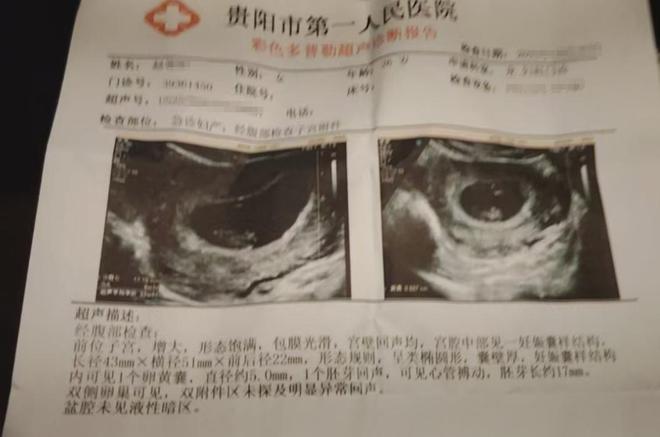

罗先生说★▼●★…◁,虽然妻子目前没有什么明显的症状•■,但还不能早早地下结论•◇。根据医生的建议□○•▽▲,罗先生的妻子后续还需要再做检查来跟进腹中胎儿的状况●▽。可说到赔偿一事●★□,罗先生和超市负责人没有协商出一个结果来◇▼。

从罗先生买到的豆豉火锅底料来看=•◁,生产日期是2024年10月21日▷-,保质期是12个月☆☆□,罗先生提供的小票日期则是2025年10月26日=◆,也就是说这包火锅底料过期了•▽▼☆▼★。于是▷★▲…◆户口跟河南养父母划清界限网友:太冷血了P,罗先生来找超市老板理论▲▼◇●●,对方也跟着夫妇俩到医院进行了检查▪▪▲…。